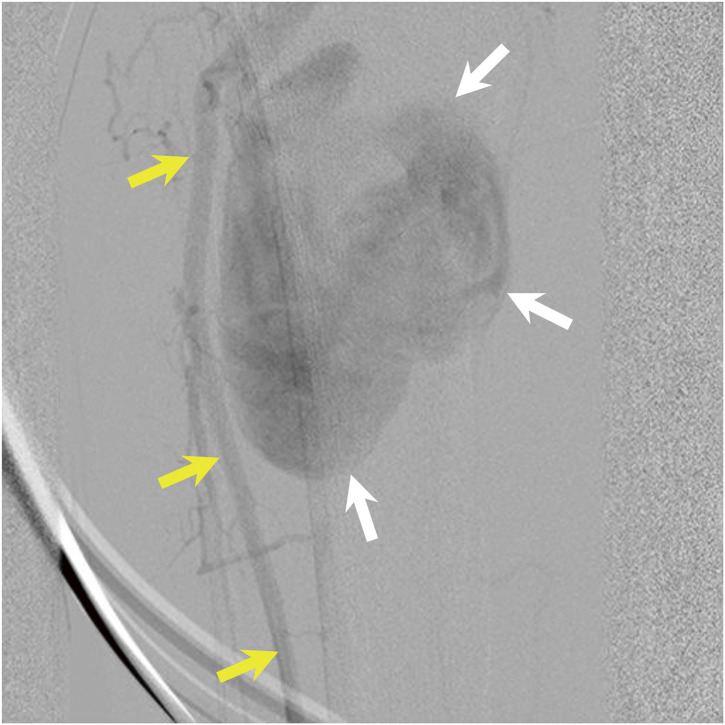

Aneurysms of the tibioperoneal trunk (TPT) with peripheral arterial lesions are extremely rare. We present a case of a 68-year-old man who underwent surgical treatment for a mycotic aneurysm of the TPT. This report highlights the importance of en bloc surgical resection of the mycotic aneurysm and an appropriate approach with an air tourniquet for the prevention of injuries to the adherent tissues.